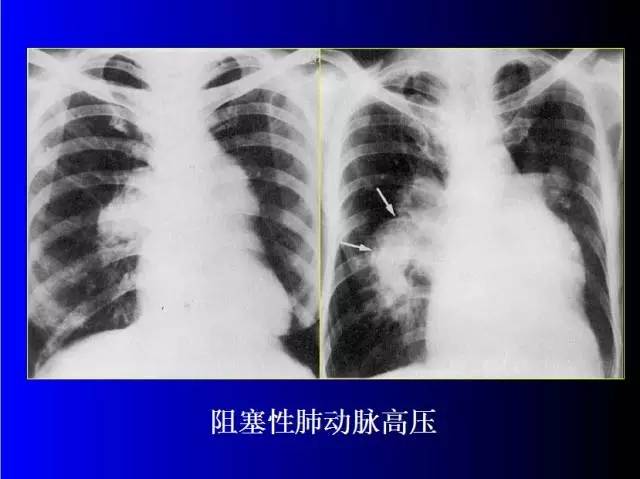

肺部基础X片及CT片解读